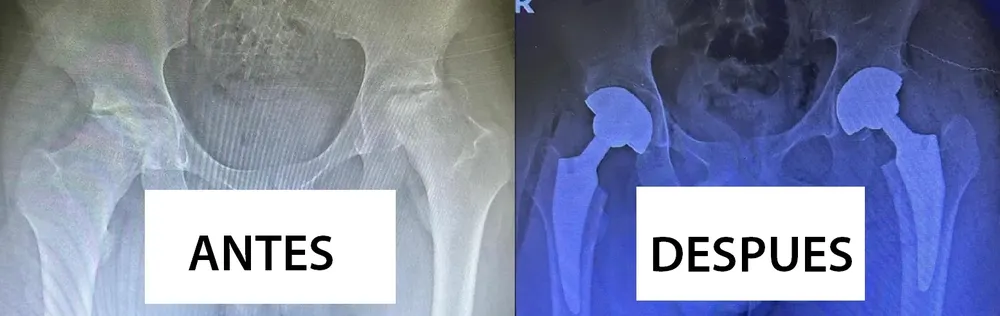

Fue tras una exitosa operación de alta complejidad que consistió en el reemplazo total de cadera a un adolescente de 16 años. El cirujano a cargo brindó detalles de la compleja intervención.

La cirugía se extendió por el lapso de dos horas, fue en un solo tiempo quirúrgico y se procedió al reemplazo de cadera bilateral, las dos piernas intervenidas en simultáneo,  situación poco frecuente ya que por lo general estas operaciones se hacen en dos tiempos de intervención quirúrgica.

Las prótesis provistas por el hospital son importadas, de cerámica, tallos cortos, de doble movilidad y con todas las características de las mejores prótesis del mercado.